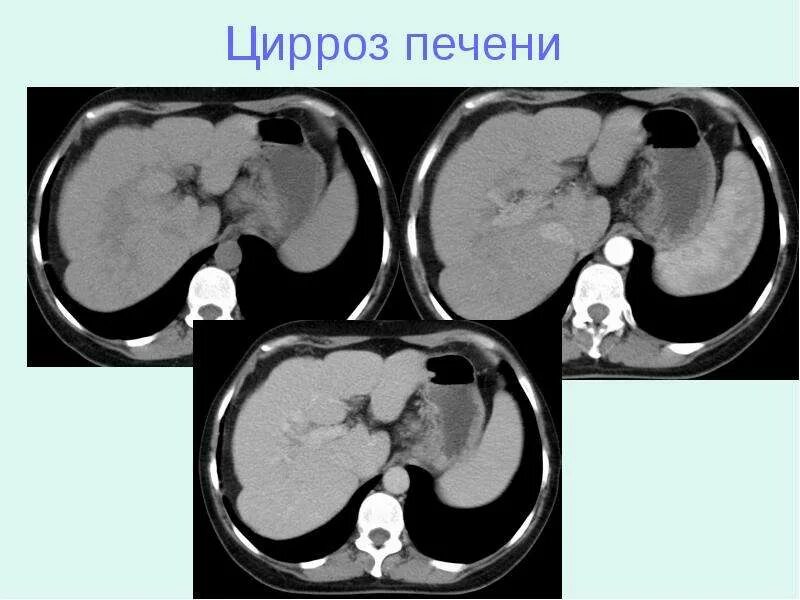

Цирроз на кт